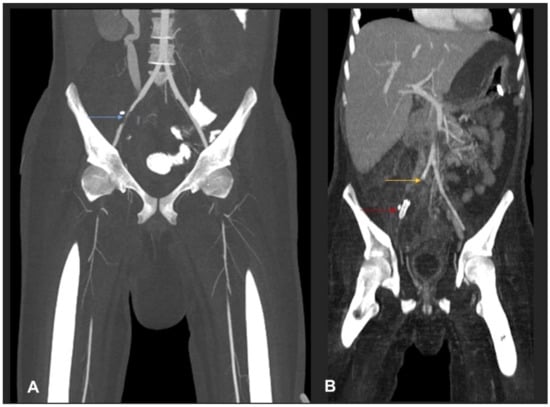

Despite the aforementioned surgical interventions and optimisation of antifungal therapy, including the empiric addition of isavuconazole (with continuation of high-dose liposomal amphotericin), the disease continued to show fulminant progression, resulting in extensive angioinvasion with involvement of the right common iliac artery, the left infrapopliteal artery and the right renal artery (Figure 4), finally resulting in bilateral lower limb ischemia and infarction of the right kidney (Figure 5).

Figure 4.

(A) MIP coronal CT angiography of aorta and lower limb shows a segmental narrowing and luminal irregularities of right external iliac artery (blue arrow). No occlusion. Distal run off was satisfactory. Rest of the lower limb vessels were patent and normal (not shown). (B) MIP coronal image of the aorta and lower limbs shows cut-off of the proximal right common iliac artery suggestive of thrombotic occlusion (yellow arrow). A stent is seen in the right external iliac artery (red arrow). Right iliac fossa shows extensive inflammatory phlegmonous mass-like soft tissue thickening.

Figure 5.

(A) MIP coronal images of abdomen shows a cut-off of the right proximal renal artery 1 cm from the ostium with adjacent inflammatory collection (blue arrow). (B) Coronal post-contrast CT shows infarction of the right kidney. A large liver abscess (yellow arrow) in the right liver lobe with extracapsular extension into the upper pole of the right kidney is also noted.